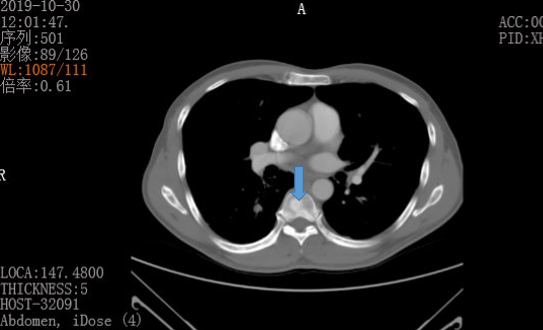

30/10日检查结果:与2019.08.20片胸部CT对比: 1、右中肺、双下肺少量炎症合并支气管扩张,同前片相仿。

2、双上肺、右下肺背段继发性肺结核,病灶以纤维增殖灶为主,合并支气管扩张,同前片相仿。 3、甲状腺右叶低密度灶,性质待定,结节性甲状腺肿?同前片相仿。

与2019.08.24片对比:

4、肝多发转移瘤,同前片大致相仿;腹膜后、肠系膜周围肿大淋巴结转移,较前片缩小。

5、肝多发小血管瘤。

6、胸骨、胸腰骶椎、骨盆及双侧股骨上段多发转移瘤。

7、乙状结肠肠壁不均匀增厚,考虑为结肠Ca,侵犯浆膜层。

8、双肾数枚小囊肿。

9、前列腺增生。CEA 1596 ug/L 。